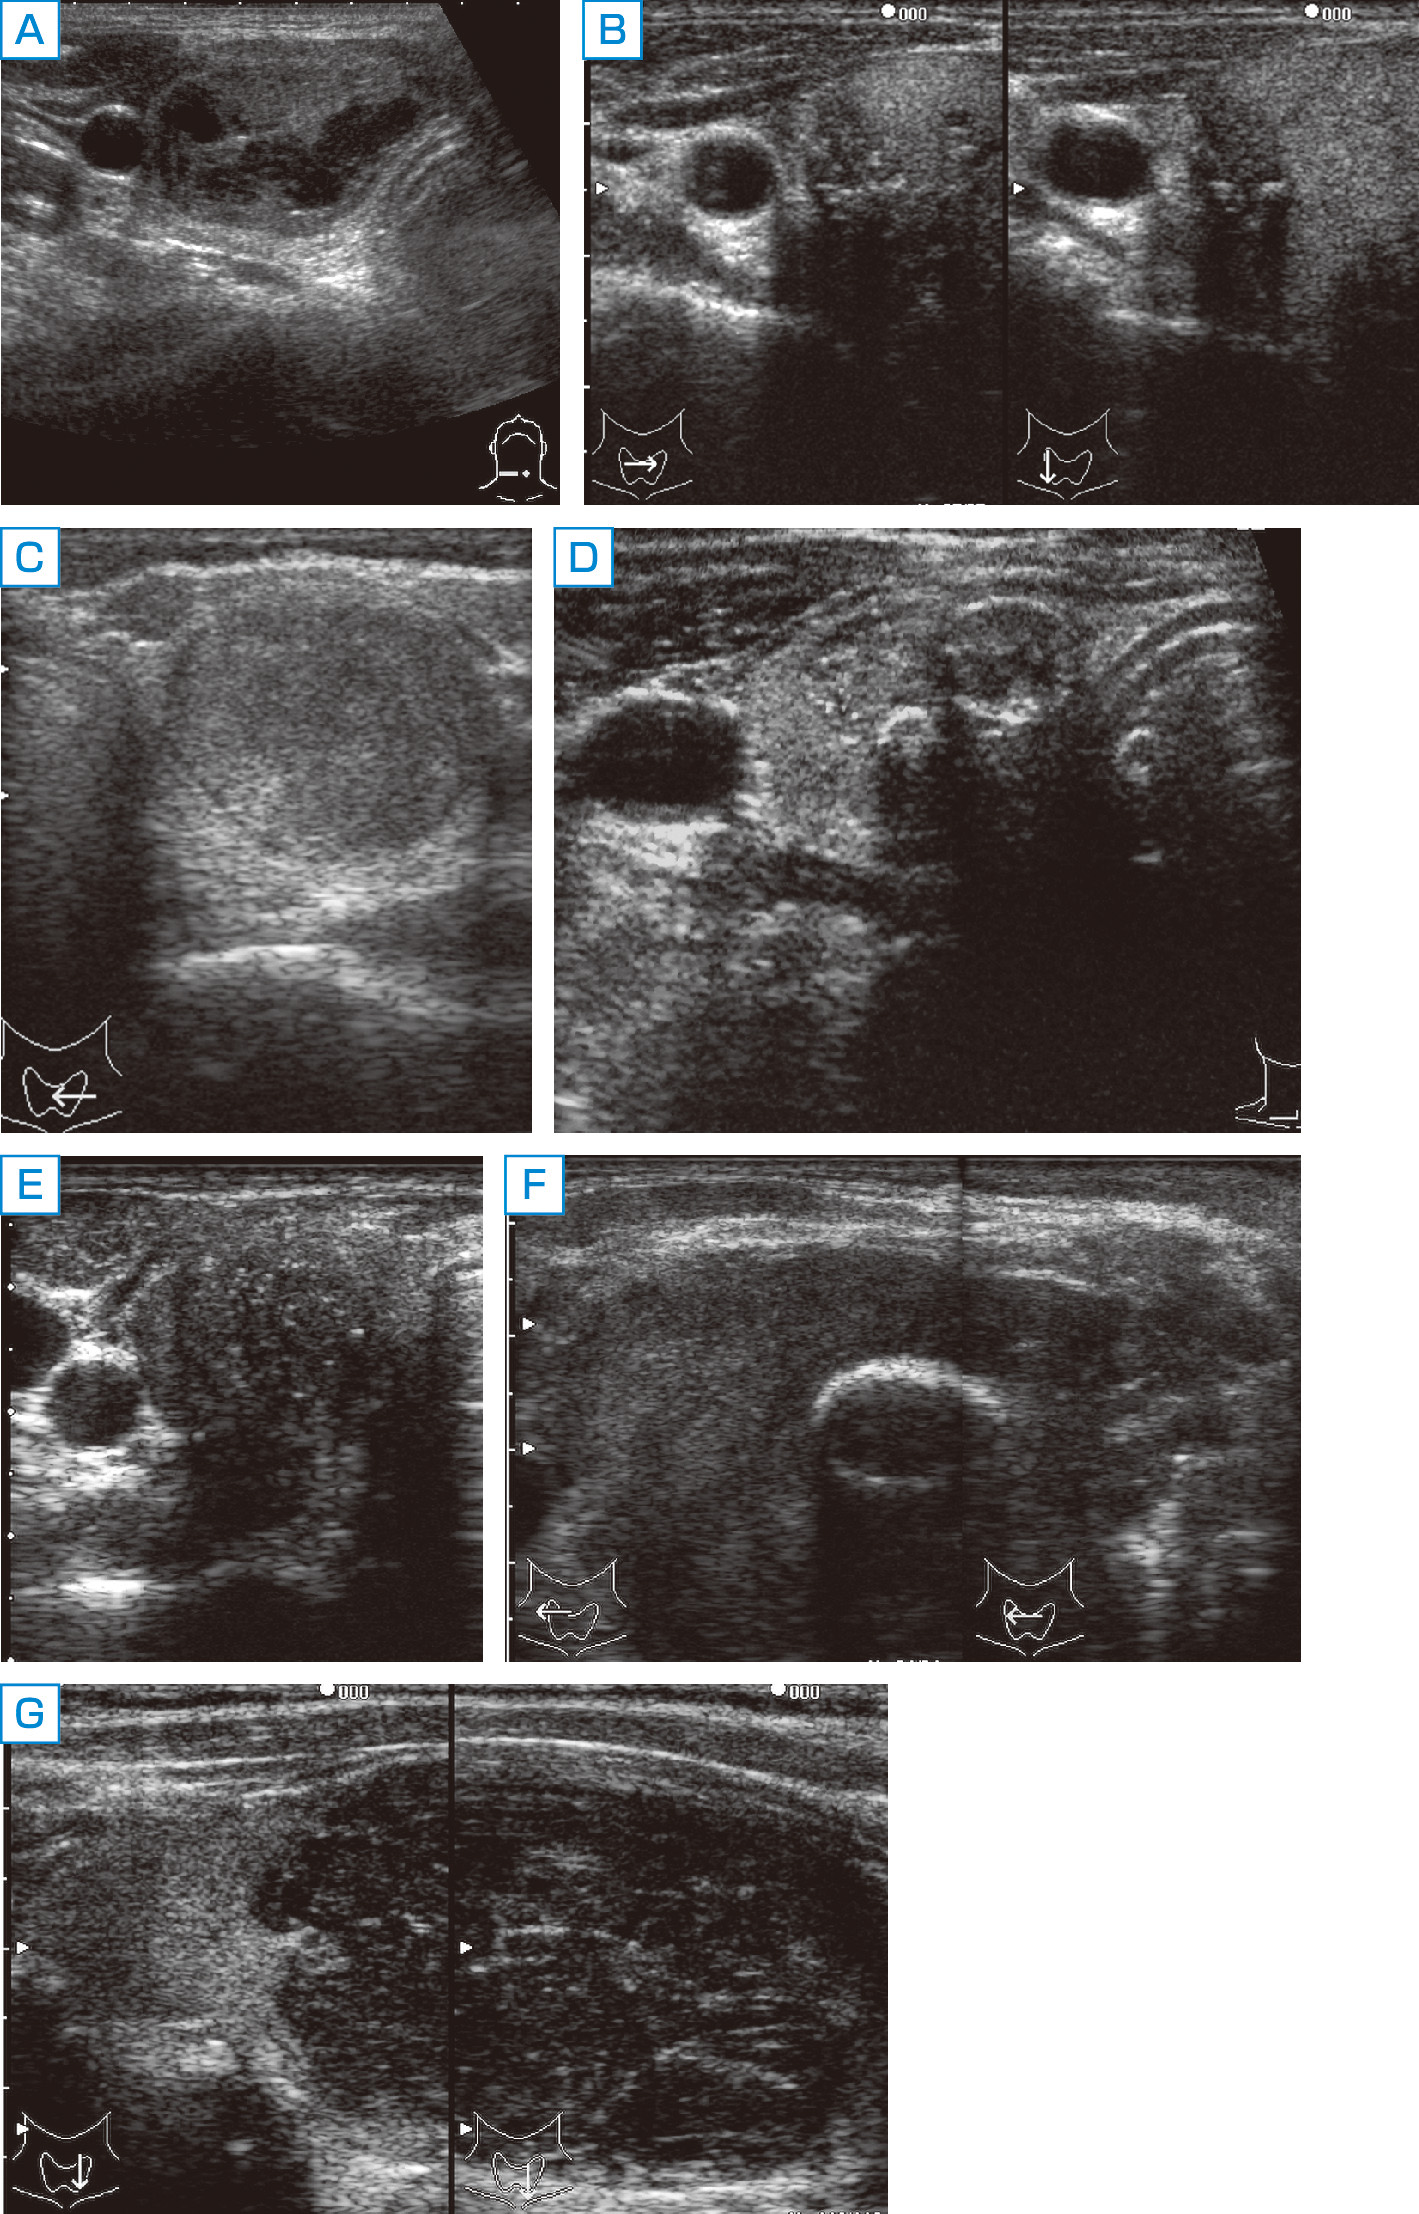

表在エコーの実学─乳腺・甲状腺・その他─ | 杉山 高 |本